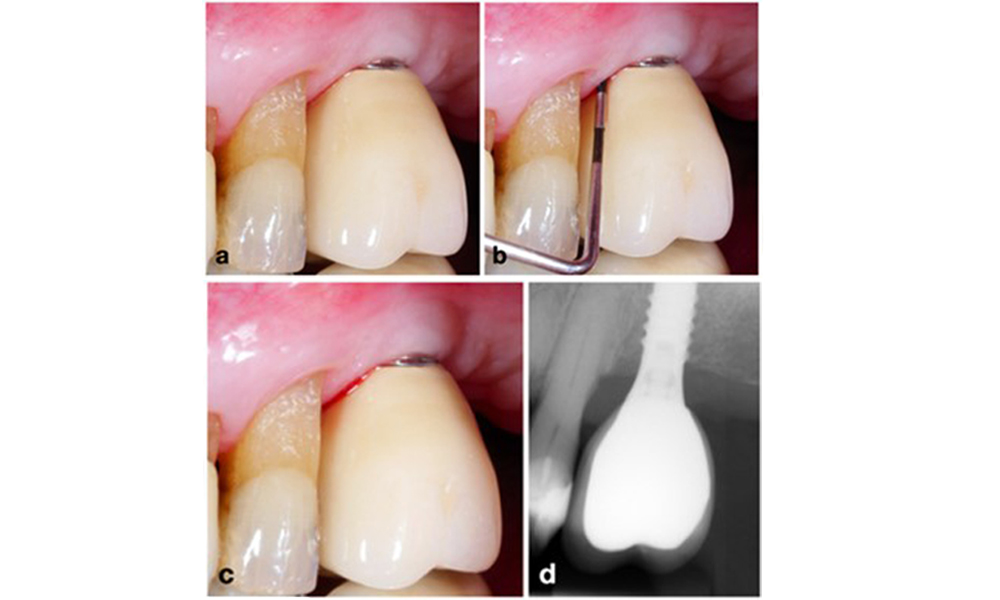

Резективен подход (т.е. гингивектомия и/или апикално позиционирано ламбо, с/без реконтуриране на костта) трябва да се избере в случаи с предимно хоризонтална костна загуба или широки дефекти, където потенциалът за костна регенерация е ограничен (фигура 11).

Пациент, лекуван с резективен подход (a). След повдигане на ламбото се наблюдава главно хоризонтална костна загуба (b), която се преодолява чрез костно реконтуриране (c) и апикално изместено ламбо, което води до сигурен следоперативен резултат (d).

Фигура 11. Пациент, лекуван с резективен подход (a). След повдигане на ламбото се наблюдава главно хоризонтална костна загуба (b), която се преодолява чрез костно реконтуриране (c) и апикално изместено ламбо, което води до сигурен следоперативен резултат (d).